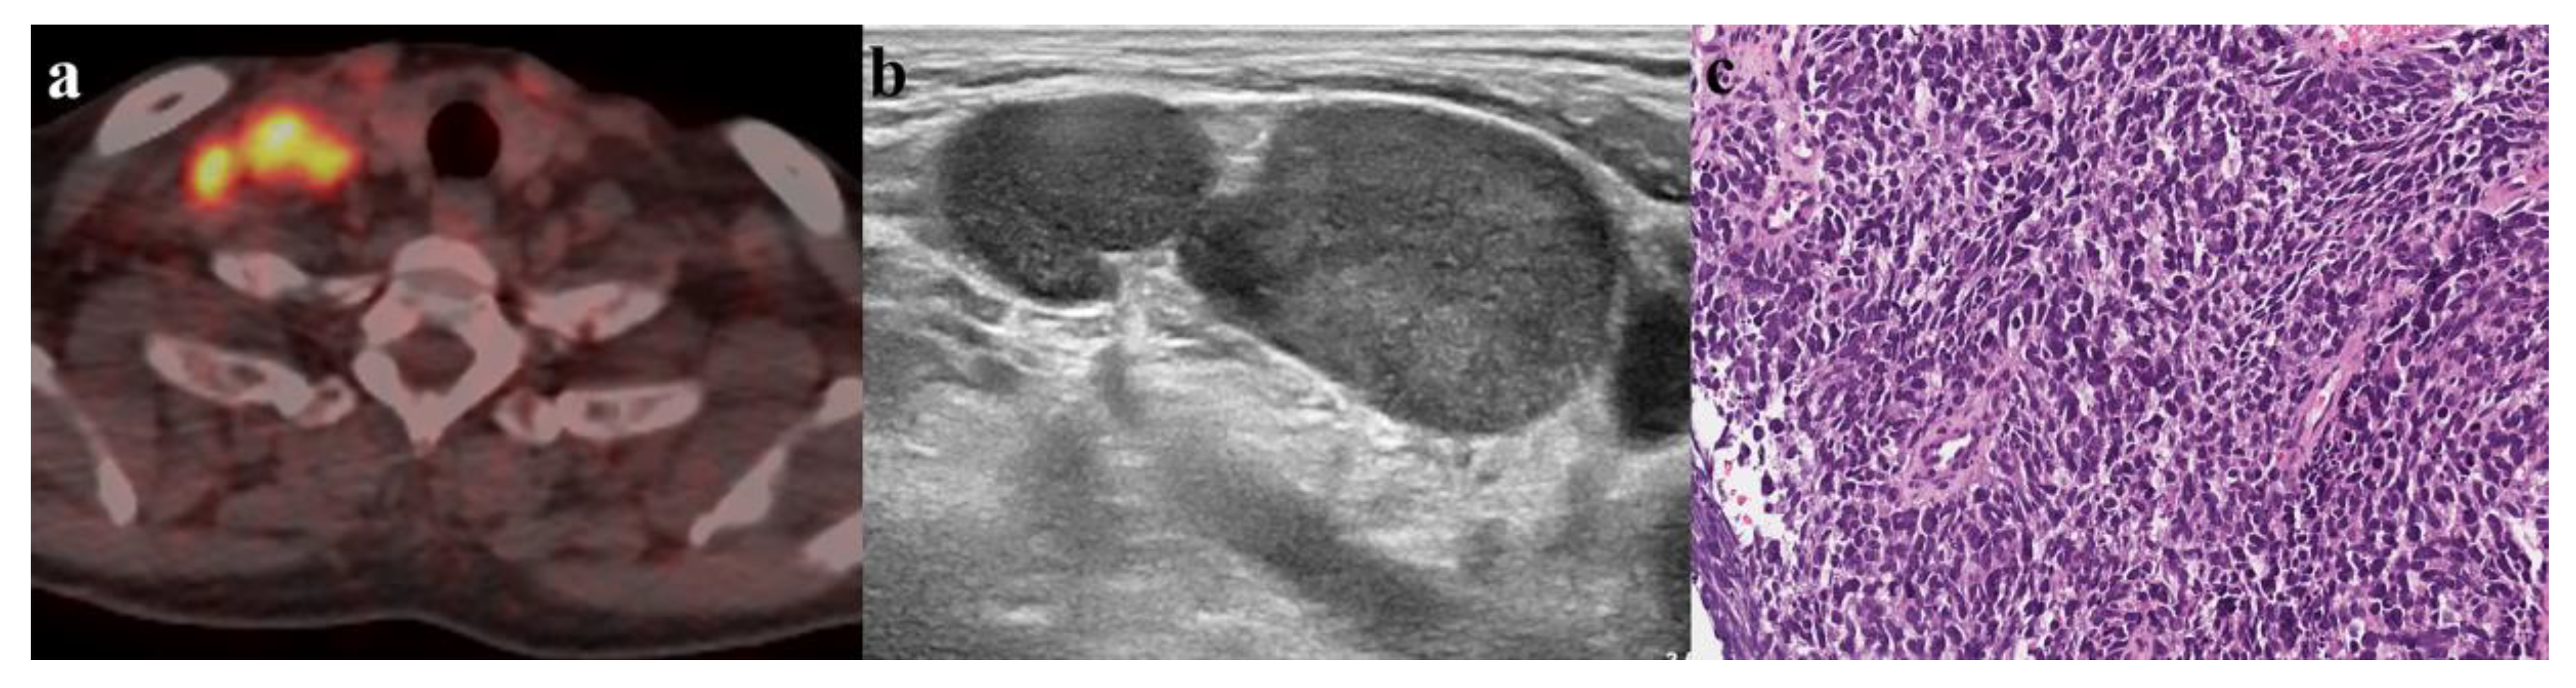

3.3. Subsequent US Findings

3.4. Combined Diagnosis Using Subsequent US Findings